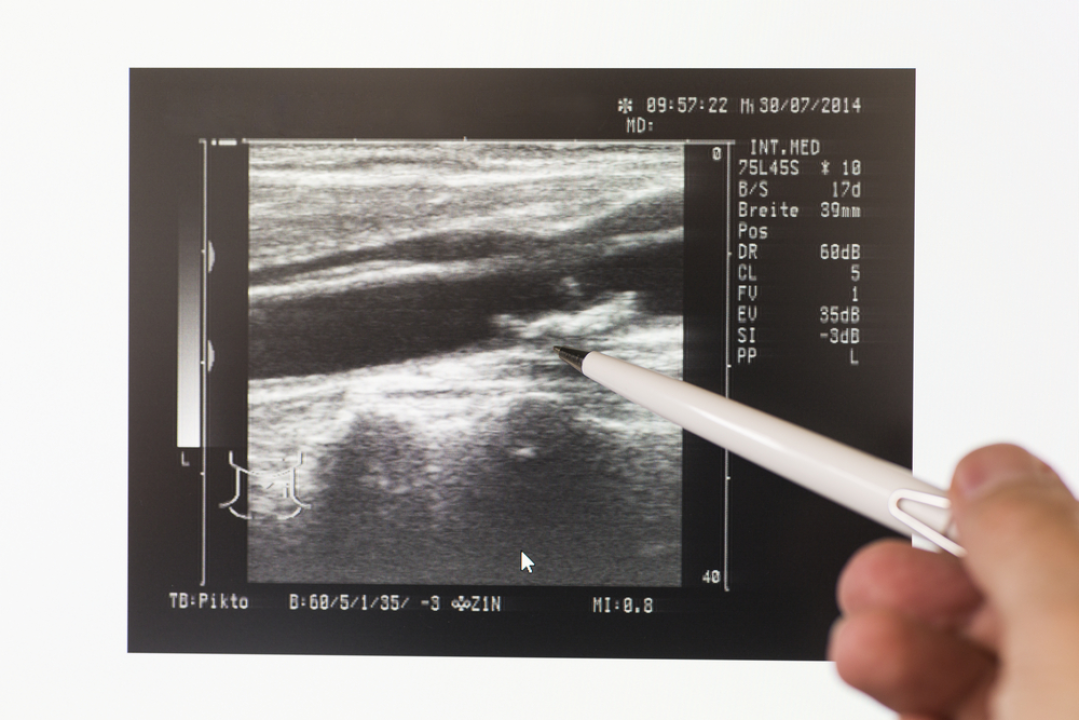

FOTO Dr. Ivan Miletić iz Poliklinike Pupillam: Moždani udar, kako što ranije otkriti aterosklerozu kao uzrok

FOTO Povodom Svjetskog dana moždanog udara, koji se svake godine obilježava 29. listopada, razgovarali smo s dr. Ivanom Miletićem, specijalistom neurologije u Poliklinici Pupillam u Zadru.